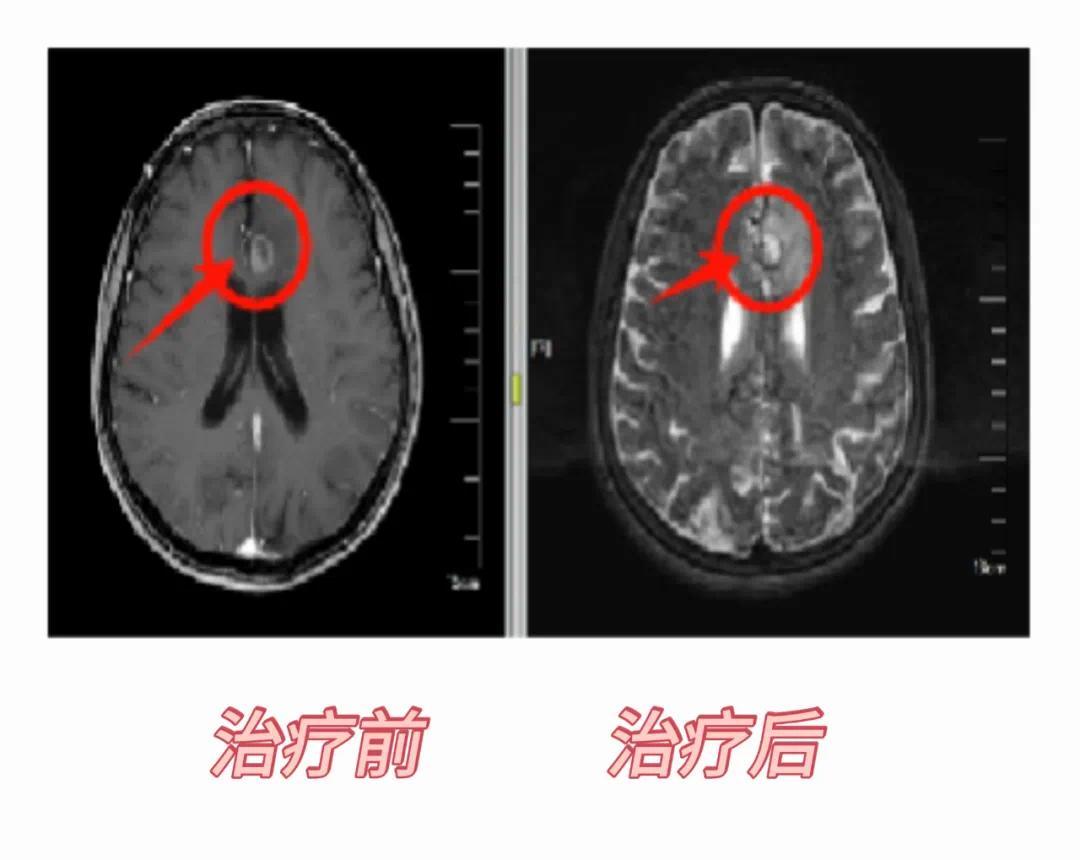

射波刀脑部病例:患者老年女性,82岁,小脑继发恶性肿瘤,综合因年龄和身体状况等因素不适合进行手术,选择行射波刀治疗7次,治疗完复查病灶失去活性,8个月后复查病灶消失。